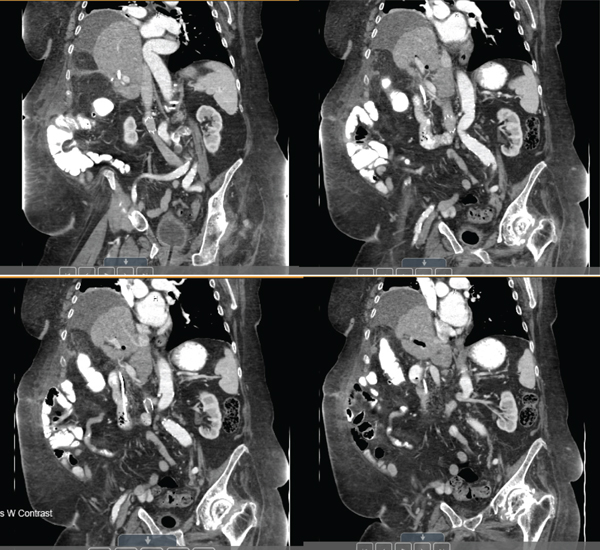

Immediately, postoperatively, the patient was managed in the intensive care unit given her instability during the operation but was transferred to a step down unit shortly after on postoperative day two. She was observed off of antibiotics with normalization of leukocytosis, remained afebrile and hemodynamically stable, and had continuously down trending bilirubin levels throughout the remainder of her hospital stay. Clinically, she recovered well and was stable for discharge on postoperative day seven with drains remaining in place and to be removed on a follow-up as an outpatient. On a subsequent follow-up, the patient was noted to remain clinically stable and follow-up CT scans revealed no intrahepatic biliary duct dilation, a normal caliber common bile duct, no intraluminal filling defect, a patent stent, and no biliary leak (Figure 4). Laboratory evaluation revealed no leukocytosis and normalization of liver enzymes and total bilirubin levels. Given these results, her surgical drains were removed, but her biliary stents remained in place, and despite multiple contact points and counseling to have a follow-up with the gastroenterologists for ERCP and removal, she was noncompliant and the stents remain in place to date. She however remains stable and healthy during her one follow-up appointment as of this writing and continues to be monitored closely with phone check-ins with no evidence of further hepatobiliary symptoms or complaints of incisional hernias.